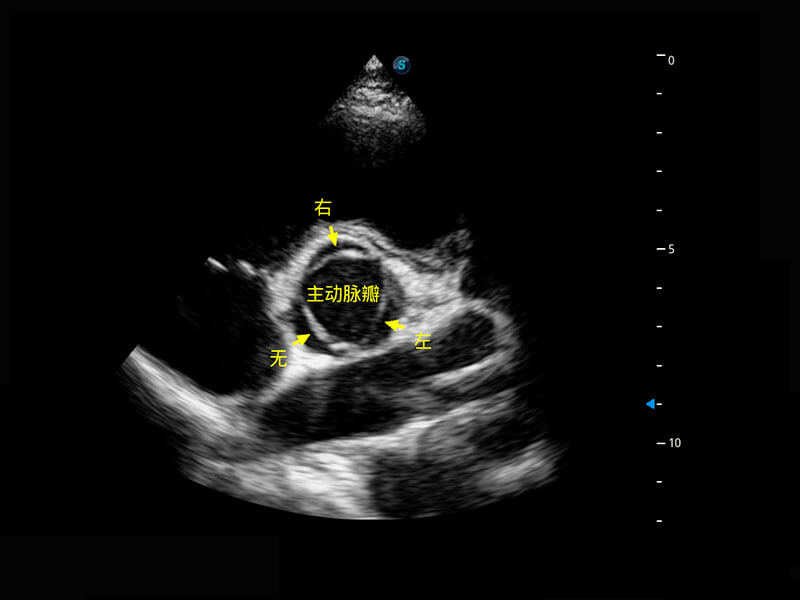

乳腺超声 / 新生儿

P60搭载宽频带线阵探头、宽景成像、弹性成像技术,为您提供乳腺应用方案。P60支持高频相控阵探头、线阵探头、腹部高频探头、腹部微凸探头等,丰富的探头群搭载敏感的彩色血流成像,适用于新生儿多种脏器检测要求,满足新生儿筛查需求。

• 新生儿脊髓圆锥

• 新生儿心脏